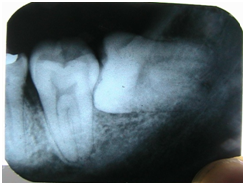

第一步:拍片

诊断结果:高位近中阻生智齿。